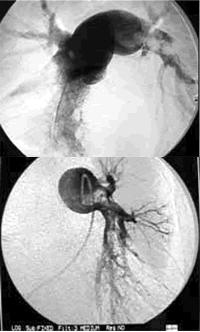

肺动脉血栓长达1米 消融术后成功取出

近日,西安交通大学医学院第一附属医院心血管内科采用肺动脉血栓消融仪,成功治疗了1例右下肢深静脉血栓形成、左右肺动脉主干及4个主要分支栓塞95%以上的大面积肺栓塞患者。血栓消融术历时3个小时,施治医师成功地从患者肺动脉中抽出直径4 mm、长100 cm余的血栓。术后患者胸痛、气短明显好转,恢复良好。